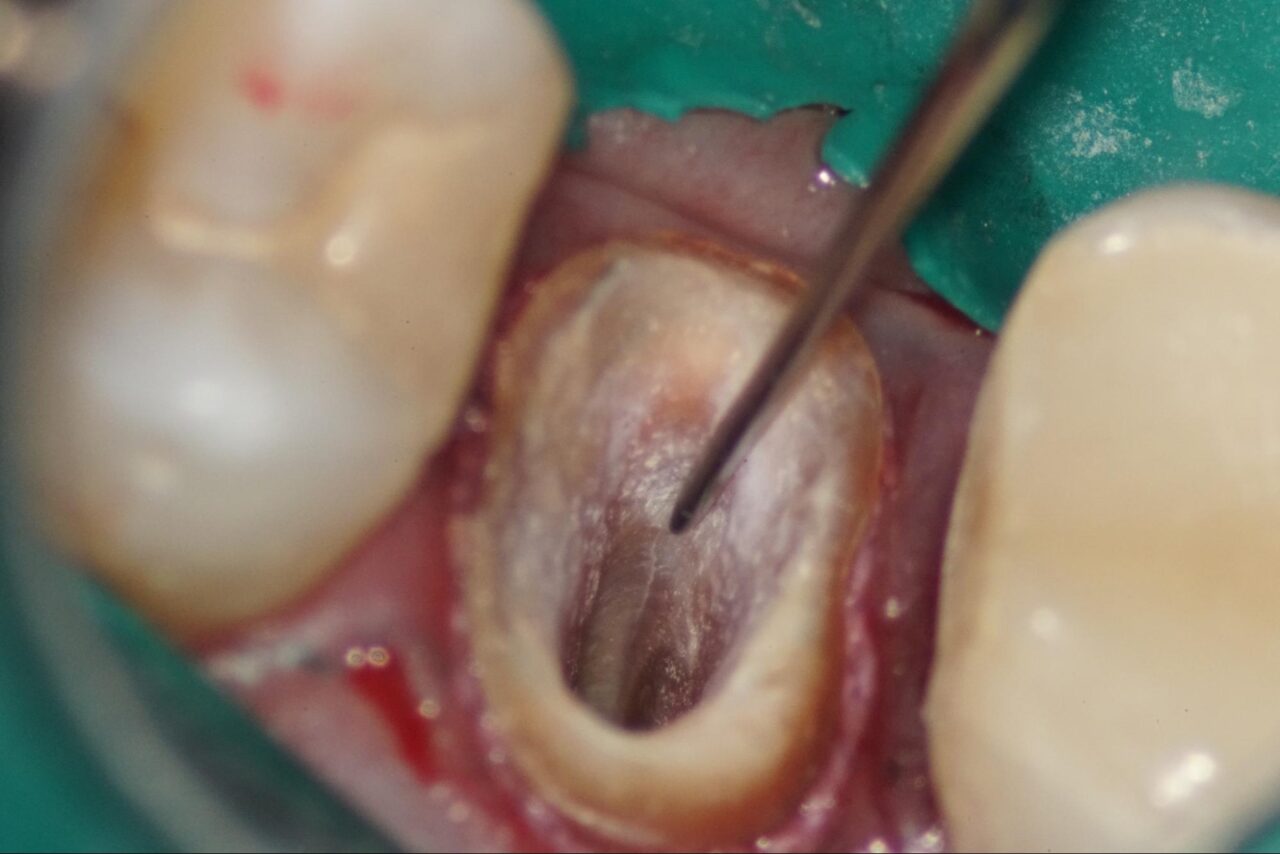

その後、ラバーダムアイソレーションを行いますが、患歯との間に何かエラーがあるためラバーシートが入って行きません。

冠を外した後にファイバーポストが入っているので、それを慎重に削って行きます。

少しずつ根管内壁が視えて来ました。

頬側根は根管が視えて来ました。よく診ると根管内壁と以前のファイバーポストの境が変色している事が確認できます。感染がそこに存在する事です。

頬側の根管内の充填物を慎重に除去して行きます。